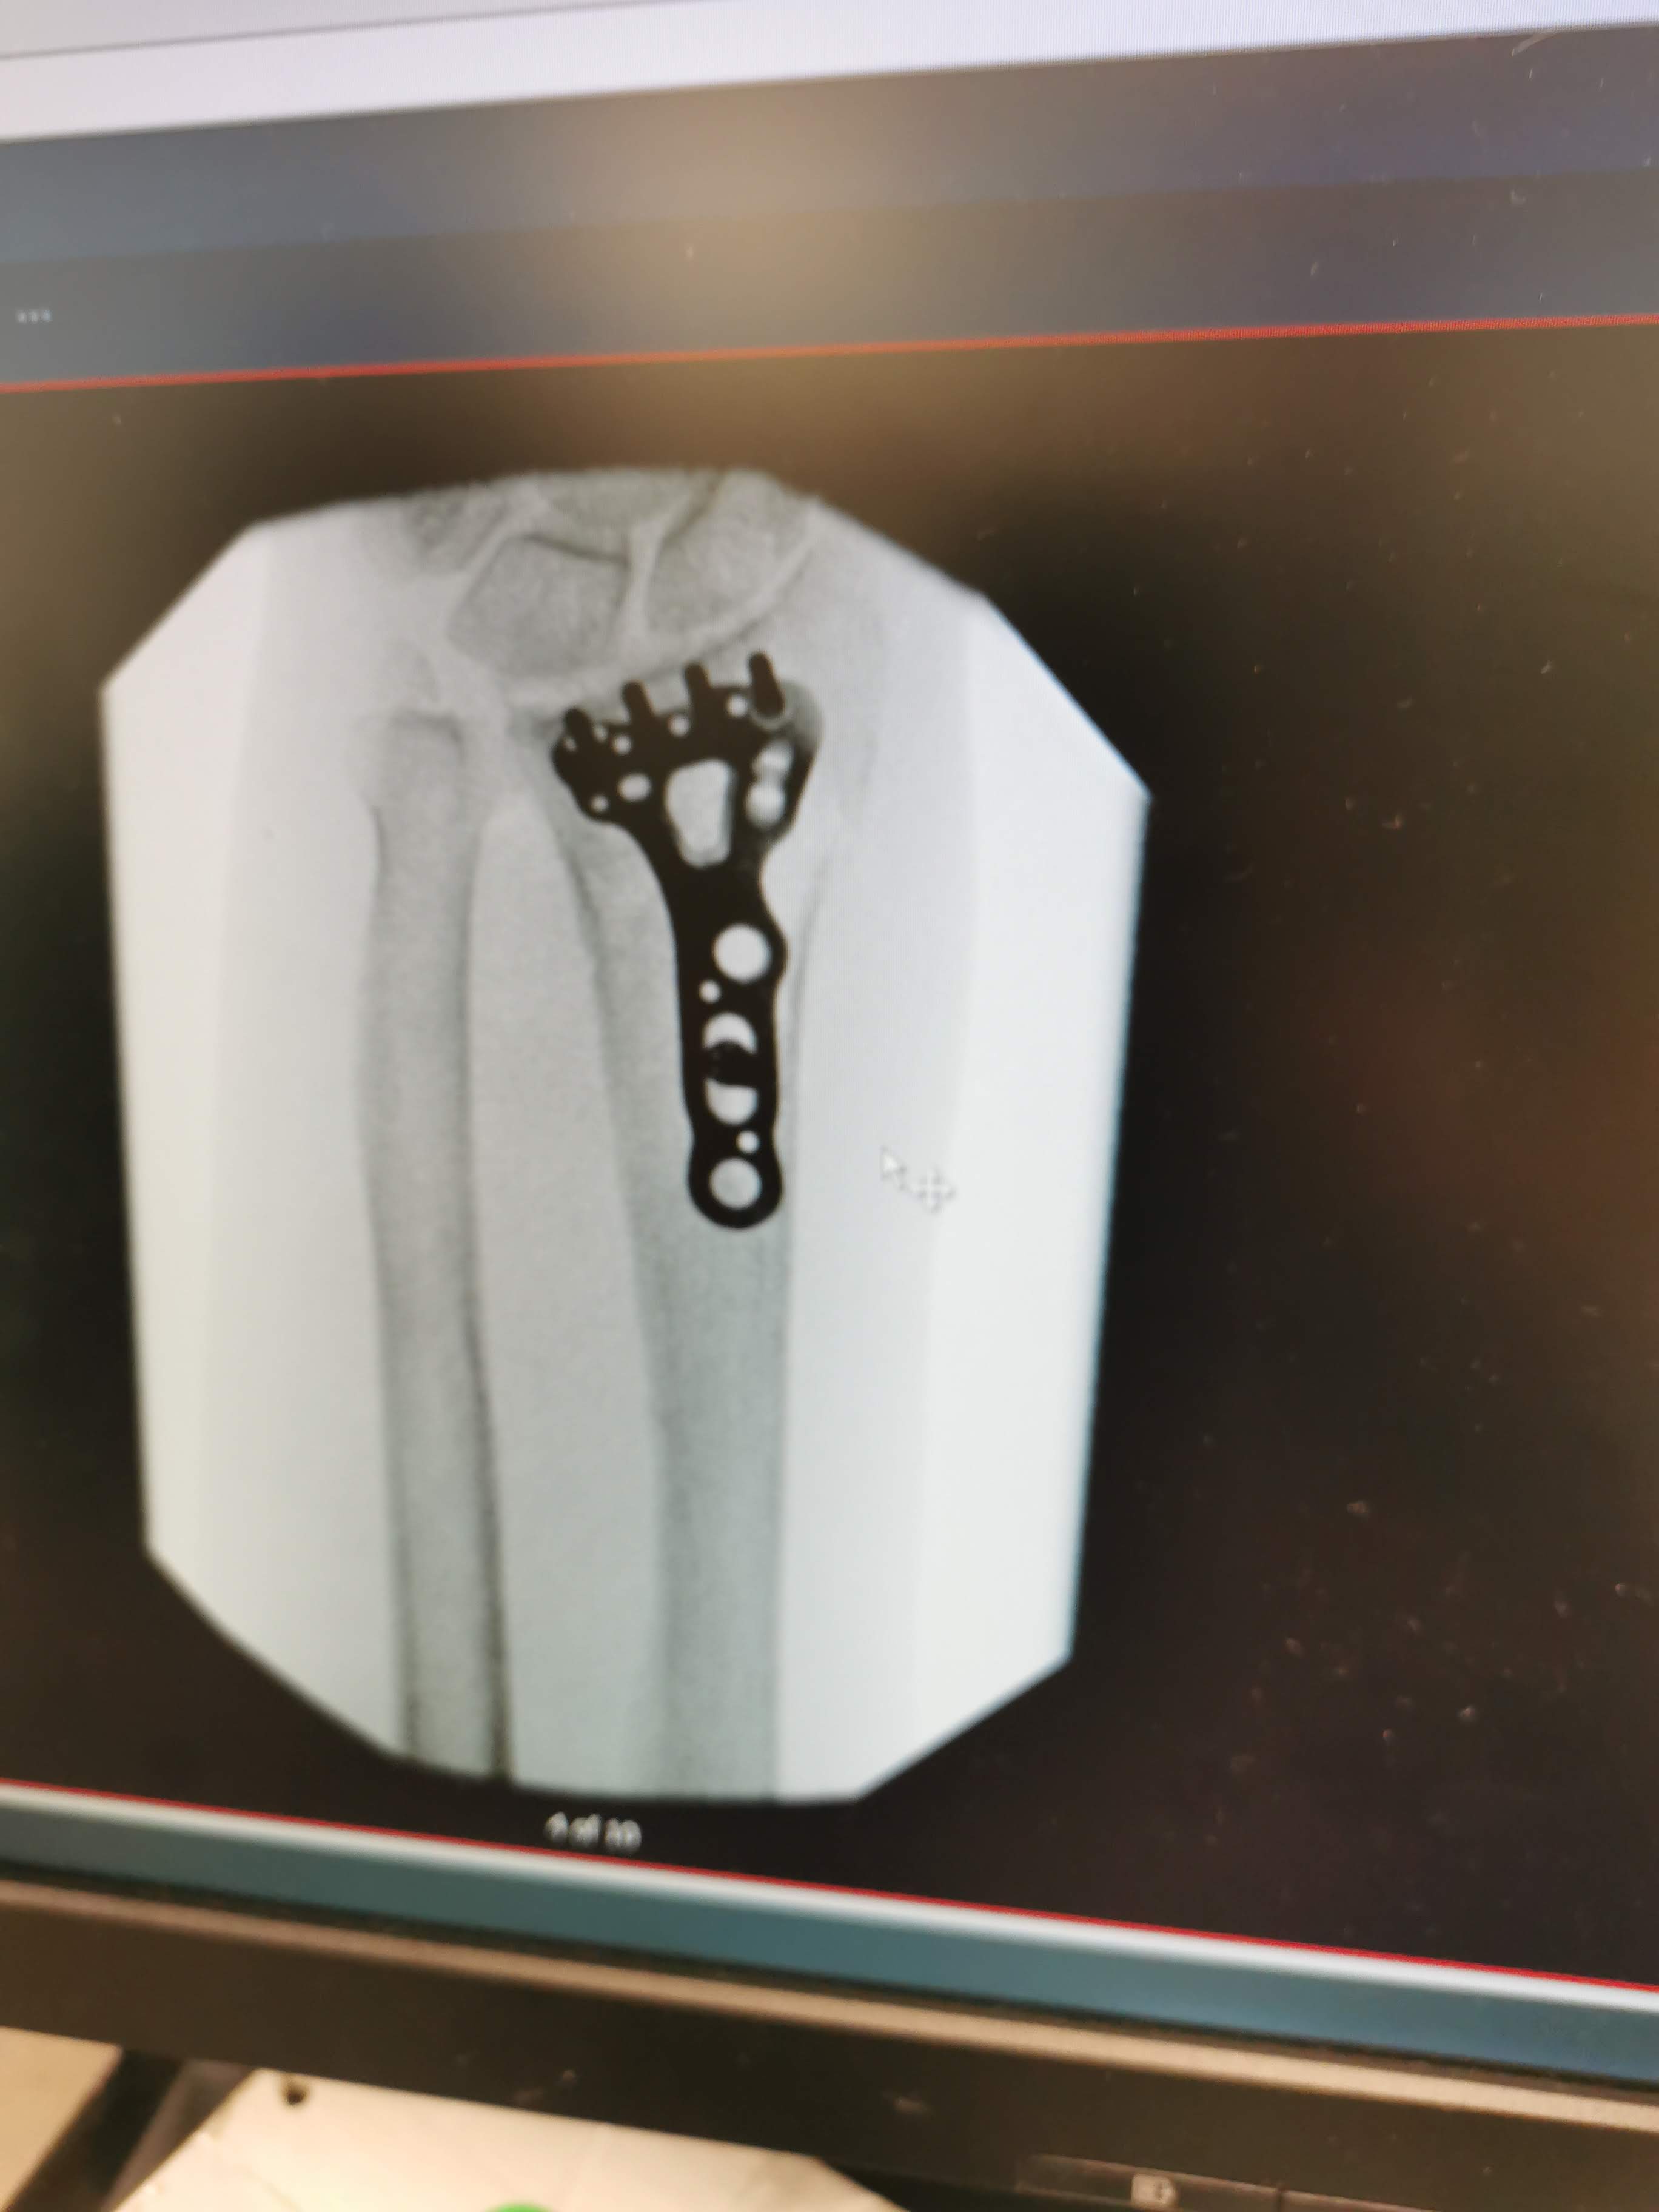

Once this had finally been done and analysed and checked by a senior doctor, it was confirmed that surgery to fit a plate was required. The next discussion was whether the surgery would be done at Auckland or Manukau hospital (where there is a specialist hand unit). In the end they opted to do things at Auckland Hospital. At which point they sent us home for the night with instructions to return the following day for the surgery.

The surgery proceeded as planned but with Sarah’s forearm now in plaster for another six weeks we were both a little reluctant to take off in the motorhome again. But we did manage to sneak a few days at Shakespear Regional Park this has become one of our go to places before Christmas. With the Pohutukawa trees in full bloom there is nothing that compares, this close to Auckland in terms of handy camping spots. We did a number of the walks in the park and on one of them followed the path through a sheep paddock. This is where the two sheep pictured aproached Sarah, maybe they sensed impending doom and wanted to be rescued from their fate. As the following day after the arrival of a large truck the paddock was empty.